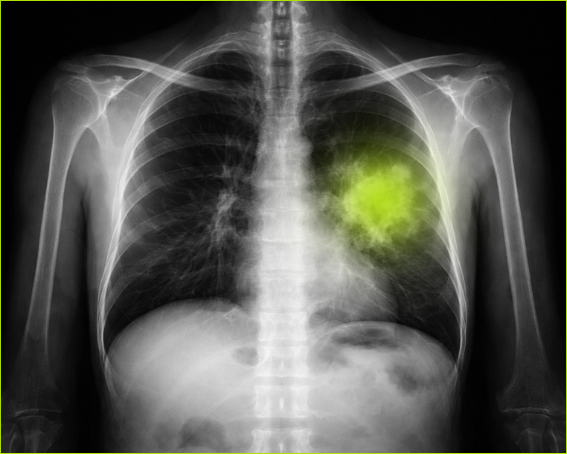

Rak płuca przez lata opisywano językiem dobrze znanym pacjentom i lekarzom – mutacje, przerzuty, tomografia komputerowa, operacja, chemia, immunoterapia. To słownik walki z jedną z najpoważniejszych chorób współczesności. Ale obok tego tradycyjnego obrazu wyrasta dziś drugi, bardziej złożony. Guz nie jest już widziany wyłącznie jako masa komórek, które wymknęły się spod kontroli. Coraz częściej przedstawia się go jako biologiczne środowisko, z naczyniami krwionośnymi, komórkami odpornościowymi, stanem zapalnym, zaburzonym metabolizmem i siecią lokalnych zależności.

Nowotwór nie rośnie w pustce. Komórki raka wydzielają substancje chemiczne, wpływają na naczynia krwionośne, zmieniają lokalny odczyn pH, przyciągają lub wypierają komórki układu odpornościowego. Wokół guza tworzy się specyficzne mikrośrodowisko. To właśnie ono interesuje dziś onkologów równie mocno jak sam guz.

Bo często o przebiegu choroby decyduje nie tylko to, jakie mutacje doprowadziły do rozwoju nowotworu, lecz także to, jak wygląda jego otoczenie. Czy układ odpornościowy jest aktywny? Czy w tkance występuje przewlekły stan zapalny? Czy guz ma dobre ukrwienie? Czy reaguje na leczenie immunologiczne?

DNA grzyba wykryto u 8 z 70 pacjentów, czyli u około 11 procent badanych. W części przypadków materiał genetyczny obecny był w wydzielinie oddechowej lub w sąsiedniej tkance płuca. Najciekawsze było jednak to, że w samej tkance nowotworowej wykryto go tylko u dwóch osób.

Oba przypadki dotyczyły gruczolakoraka płuca o wysokim stopniu złośliwości.

– W naszych obserwacjach grzyb ten był wykrywany w tkance nowotworowej u pacjentów z bardziej zaawansowaną postacią nowotworu, co może sugerować, że takie zmienione środowisko guza sprzyja kolonizacji Pneumocystis. Trzeba jednak podkreślić, że jest to wstępna obserwacja i wymaga dalszych badań – podkreśla dr Szydłowicz.

To obserwacja interesująca, ale wymagająca dużej ostrożności. Dwa przypadki nie są podstawą do szerokich uogólnień. Mogą jednak sugerować kierunek dalszych badań. Być może bardziej agresywne nowotwory tworzą środowisko bardziej podatne na kolonizację przez niektóre mikroorganizmy.